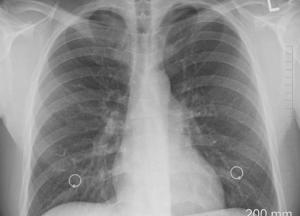

Наиболее распространенные формы рака легких образуются в дыхательных путях, ведущих в легкие. Если опухоль препятствует прохождению дыхательных путей, это также может вызвать одышку, хрипы и постоянный кашель, который может включать кровь и мокроту. Опухоль, расположенная в верхней части легкого, может оказывать давление на нервы и кровеносные сосуды, идущие в руку, вызывая боль и слабость в конечности.

Это может сопровождать стойкое ощущение покалывания. Более ранний признак, который бывает трудно обнаружить, - это стук в пальцах, когда кончики пальцев наполняются кровью из-за недостатка кислорода.

В некоторых случаях опухоль может давить, препятствуя току крови к голове, что приводит к отеку вокруг лица. Признаки, общие с другими формами рака, включают усталость и потерю веса.

В некоторых случаях опухоль легких может выделять большое количество гормонов, которые вызывают симптомы в более отдаленных частях тела.

Рак легкого может совпадать с другими легочными инфекциями. Если у вас легочная инфекция, которая не поддается лечению антибиотиками или другими методами лечения, ваш врач может провести обследование на предмет рака легких.

Рак легких часто распространяется быстрее, чем другие формы рака, при этом раковые клетки распространяются через кровь, которая проходит через легкие и попадает в остальную часть тела.